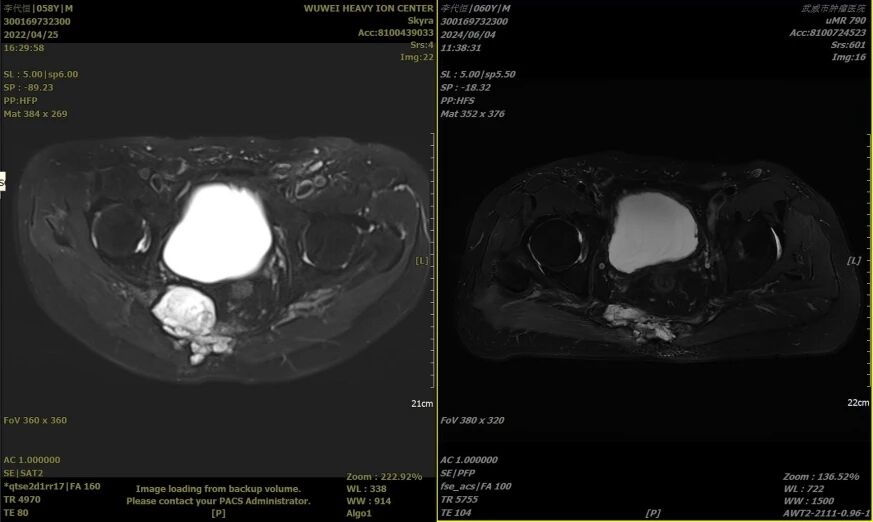

三、患者男,58岁,骶尾部脊索瘤,2022年5月25日行重离子治疗。

治疗前2022年4月25日 治疗后2024年6月4日